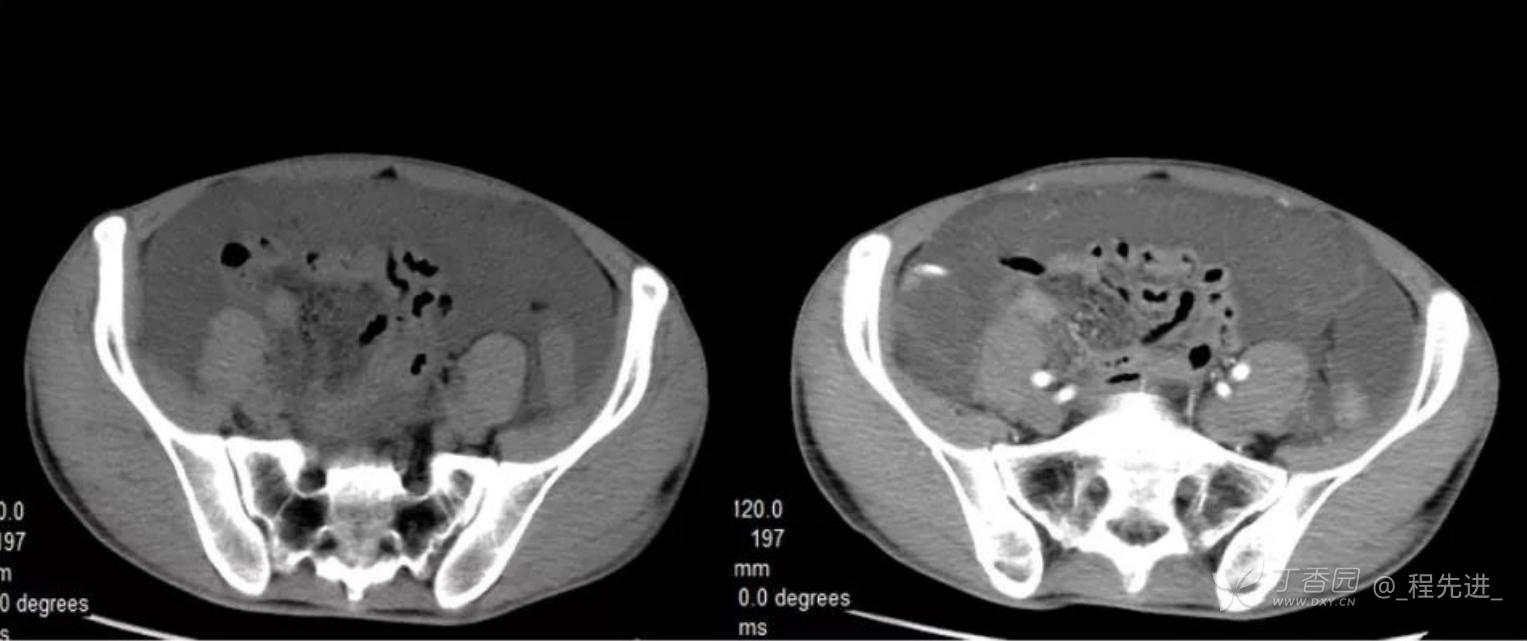

患者性别:男

患者年龄:46岁

主诉:腹胀10余天

现病史:患者10余天前无诱因腹胀,进食后加重,便后缓解,余无特殊

腹膜假黏液瘤 (5)